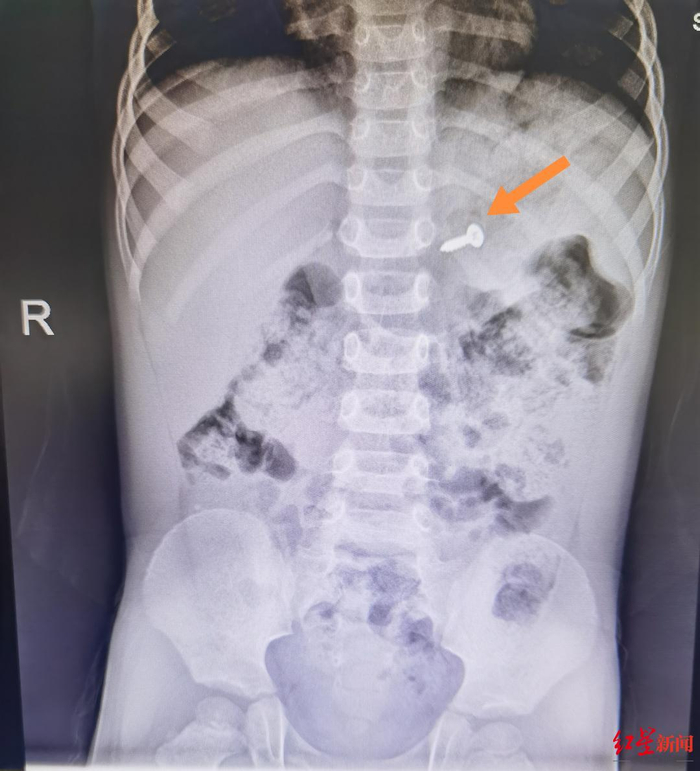

2月1日晚上,发现孩子误吞了异物,家长赶紧把孩子送到四川省人民医院急诊科,值班医生通过检查发现,孩子体内确实有异物,从外形看,是一枚小螺丝钉,已经进入了孩子的胃部。覃道锐解释说,小儿消化道异物很常见,按照异物的不同性质,有不同的处理方案和经验,例如这类4.5厘米以下的长形异物,比较小,还是有较大机会能随着排便自行排出的。

▲2月1日,螺丝钉在患儿胃部